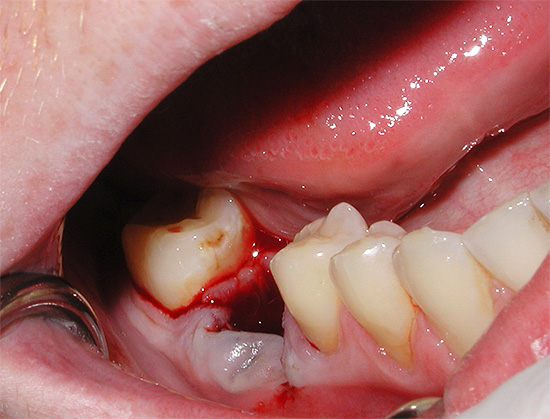

- Remoção do dente do siso retardado inferior (isto é, que não pode cortar adequadamente). Como regra, a operação para removê-lo é bastante traumática, durante a qual o médico disseca a gengiva e, às vezes, para um melhor acesso, expande bastante a ferida.Devido ao grande número de tecidos bem supridos de sangue, removendo o dente do siso inferior freqüentemente ocorre sangramento abundante e, com lesões significativas nos ossos e na gengiva, um inchaço na bochecha ocorre no primeiro dia após a remoção do dente "sábio".